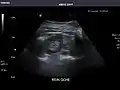

Left kidney

Kidneys: Right and left kidneys measure 11.5 cm and 12 cm in length respectively. No hydronephrosis. Small left lower pole kidney cyst.